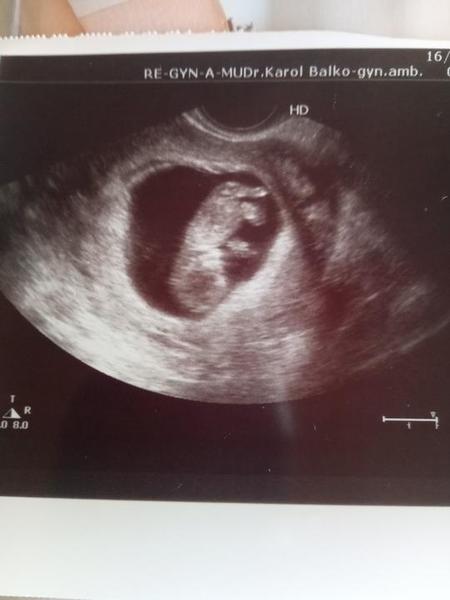

Mame len hlavičku s ručičku v pusinke odfotene lebo sa nedala odfotit 😄 ta bude po mame!! Ani ja sa nemusím fotiť jehe

@123vika ale tak specialne pre teba 😘 podoba je jednoznacna,cela ja 😂

@123vika mne sa skor podoba na moju macku ked spi 😂 😂

@123vika no to je utešená fotkaaaaa, princeznička malinká😍

@123vika jeeeeeeeeeeeeeeeeeeeeeej 😍 to si cmula prst? 🙂